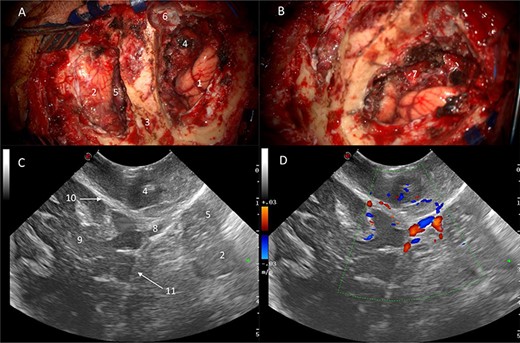

Ultrasound (B-mode) was used to identify the tumour margins, tentorium and venous structures (Fig. 2). Combined with the B-mode, Doppler ultrasound (US) was employed to assess the presence and direction of flow in the right transverse sinus, torcula and superior sagittal sinus. There was presence of blood flow in all these dural venous sinuses, however, the flow within the straight sinus was only unidirectional towards the torcula from the vein of Galen and from the tentorium tributary veins. The unique feature of the intracranial venous sinuses is that blood flow is bi-directional as they lack valves. Hence, this finding suggests there was a degree of venous insufficiency due to obstruction of the venous sinuses engulfed by the meningioma (Fig. 2).

IoUS initial assessment; (A) B-mode image of the surgical field; 1, supratentorial tumour; 2, infratentorial tumour; 3, tentorium; 4, straight sinus; 5, contralateral occipital lobe; 6, falx; (B) triplex Doppler of the straight sinus: combined 2D image with overlay of the colour and pulse wave Doppler demonstrating unidirectional flow from the vein of Galen and the tributary veins of the tentorium.